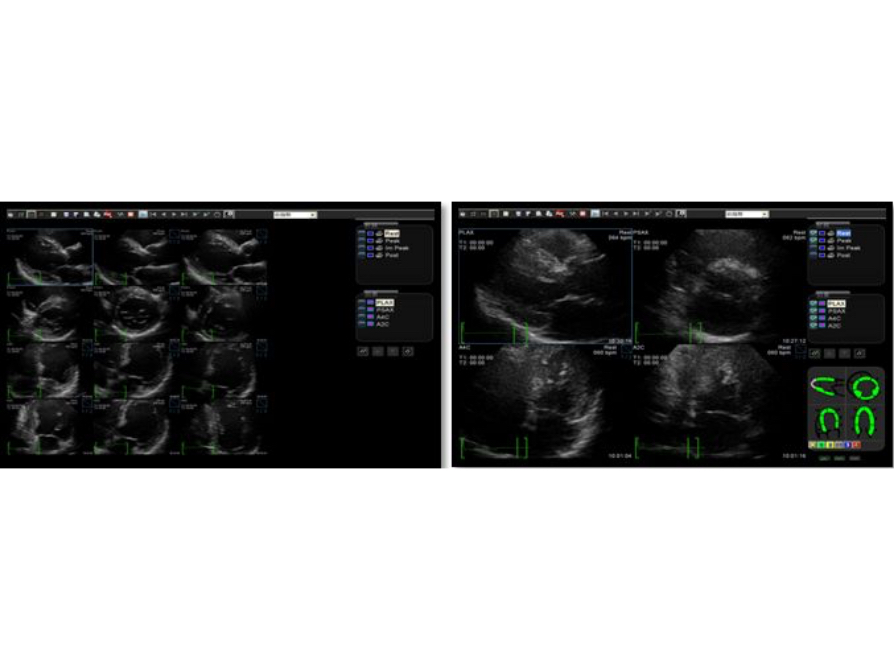

Gain accurate measurement of the myocardial function in response to external stress or pharmacy.

Gain precise anatomical observation by freely placing sample lines at any angle. Attain better images through simultaneous display of up to 3 sample lines.

Accurately evaluate myocardial motion at different phases, and simultaneously determine myocardial synchronization. High frame-rate providing you with accurate results.